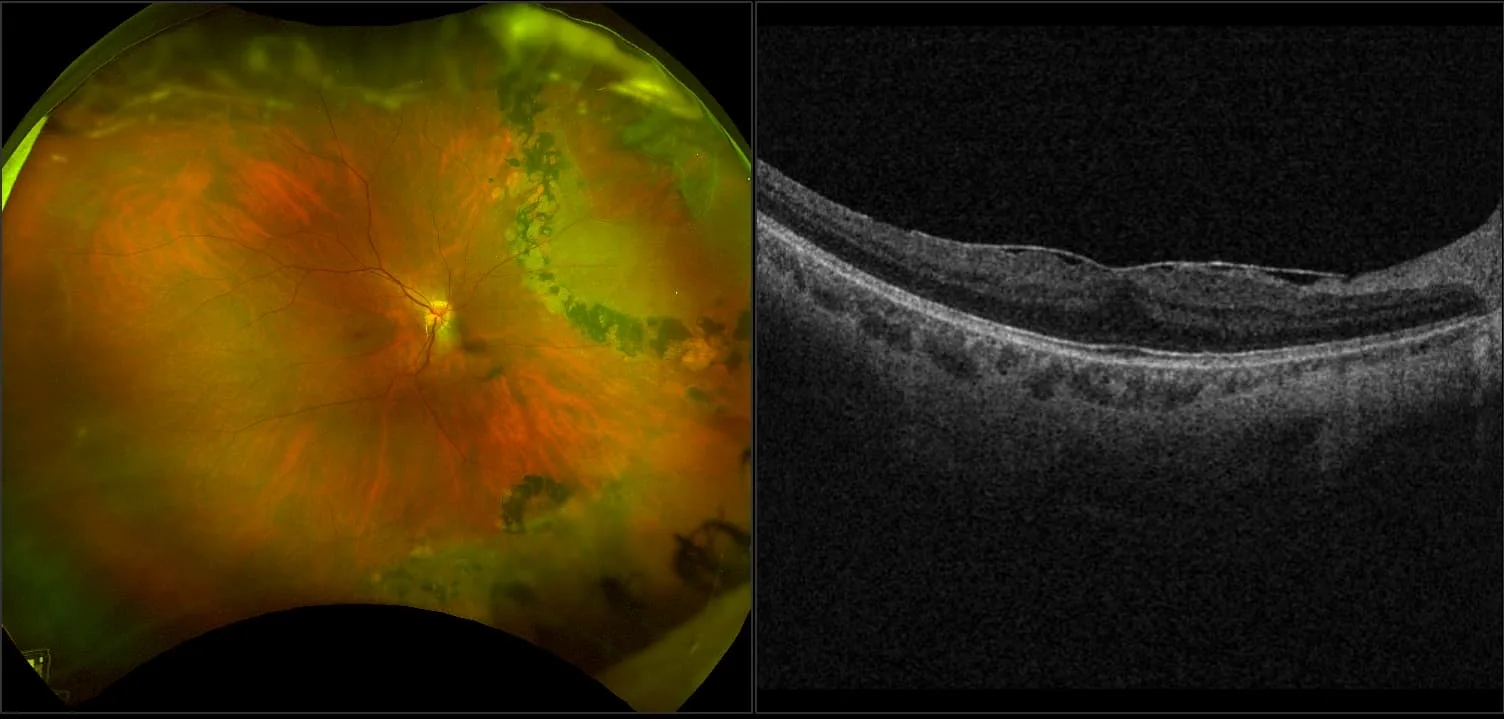

MonacoPro - Epiretinal Membrane RG, AF, OCT

An epiretinal membrane is a fibrocellular tissue found on the inner surface of the retina. It is semi-translucent and proliferates on the surface of the internal limiting membrane.